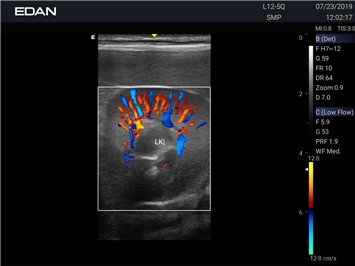

Ветеринарный ультразвук одним нажатием. Система Acclarix AX2 VET разработана с целью обеспечить бескомпромиссную производительность по доступной цене. Наличие уникальных двойных аккумуляторов в легком корпусе массой 4,5 кг из магниевого сплава позволяет системе Acclarix AX2 VET удовлетворять все потребности ветеринарных исследований, сохранив низкую стоимость.

EDAN Acclarix AX2 VET представляет собой специализированную ветеринарную ультразвуковую систему, сочетающую высокую производительность с доступной ценой. Благодаря продуманной конструкции и передовым технологиям, система обеспечивает качественную диагностику животных различных видов.

Энергетический допплер:

Цветовой допплер: